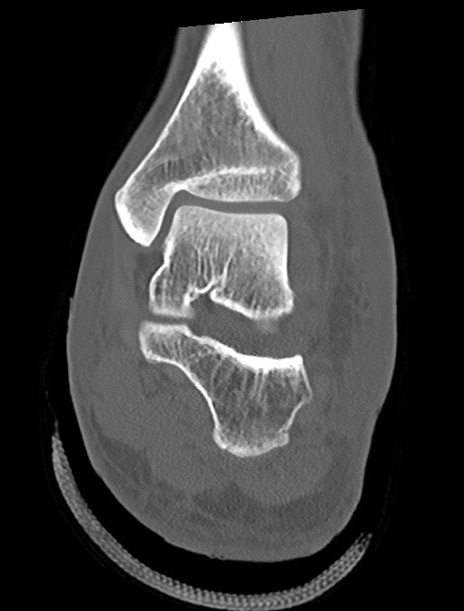

左足関節CT

矢状断像